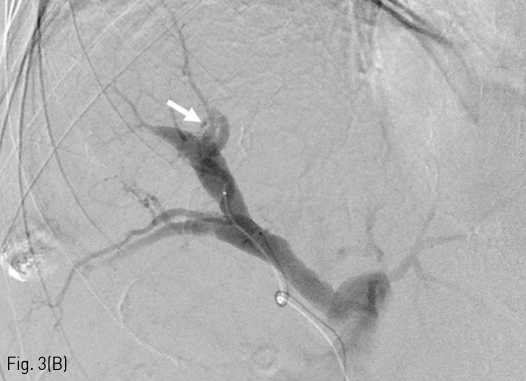

Fig 3A

Embolization of massive arterioportal shunt. The common hepatic arteriography (A) and S7 segmental hepatic arteriography (B) showed massive arterioportal shunt (arrowhead) between a branch of the S7 segmental hepatic artery and right posterior portal vein. A connection (arrow) between the S7 segmental hepatic artery and right posterior portal vein was identified on arteriography.